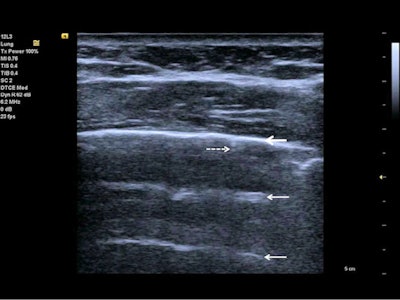

Lung ultrasound using a linear probe. B-lines (white arrows) with irregular pleura and a small pleural effusion (bold white arrow).Lung ultrasonography can be used for quick evaluation of the severity of SARS-CoV-2 pneumonia, to track the evolution of disease during follow-up, and to monitor lung recruitment manoeuvres. Additionally, ultrasonography can track the response to prone-position ventilation and the controlling of extracorporeal membrane therapy.